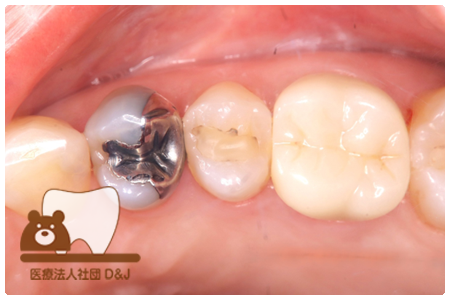

症例4フルジルコニアクラウン 左下6

治療前

治療後

37歳 男性

- 治療内容

- 以前のクラウンがセメントの劣化により外れた為その上にフルジルコニア製の被せ物を装着しました。見た目と強度を両立した自由診療の治療です。

- 治療期間

- 1カ月

- 費用

- 自費

フルジルコニアクラウン:77,000円(税込)

(R8.1月時点)

- その他の治療の費用は含まれておりません。

- リスク・副作用

- 硬い素材のため、かみ合う歯に負担がかかることがあります。将来取り外す場合に歯に負担がかかることがあります。強い力が加わると、まれに欠けたり割れたりすることがあります。